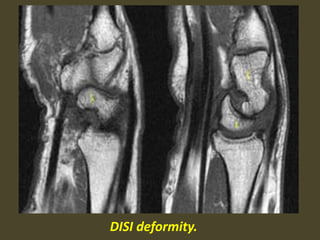

DISI deformity.

DISI.

1. Scapholunate ligament tear, dorsal angulation of the lunate and

proximal migration of the capitate consistent with a DISI deformity.